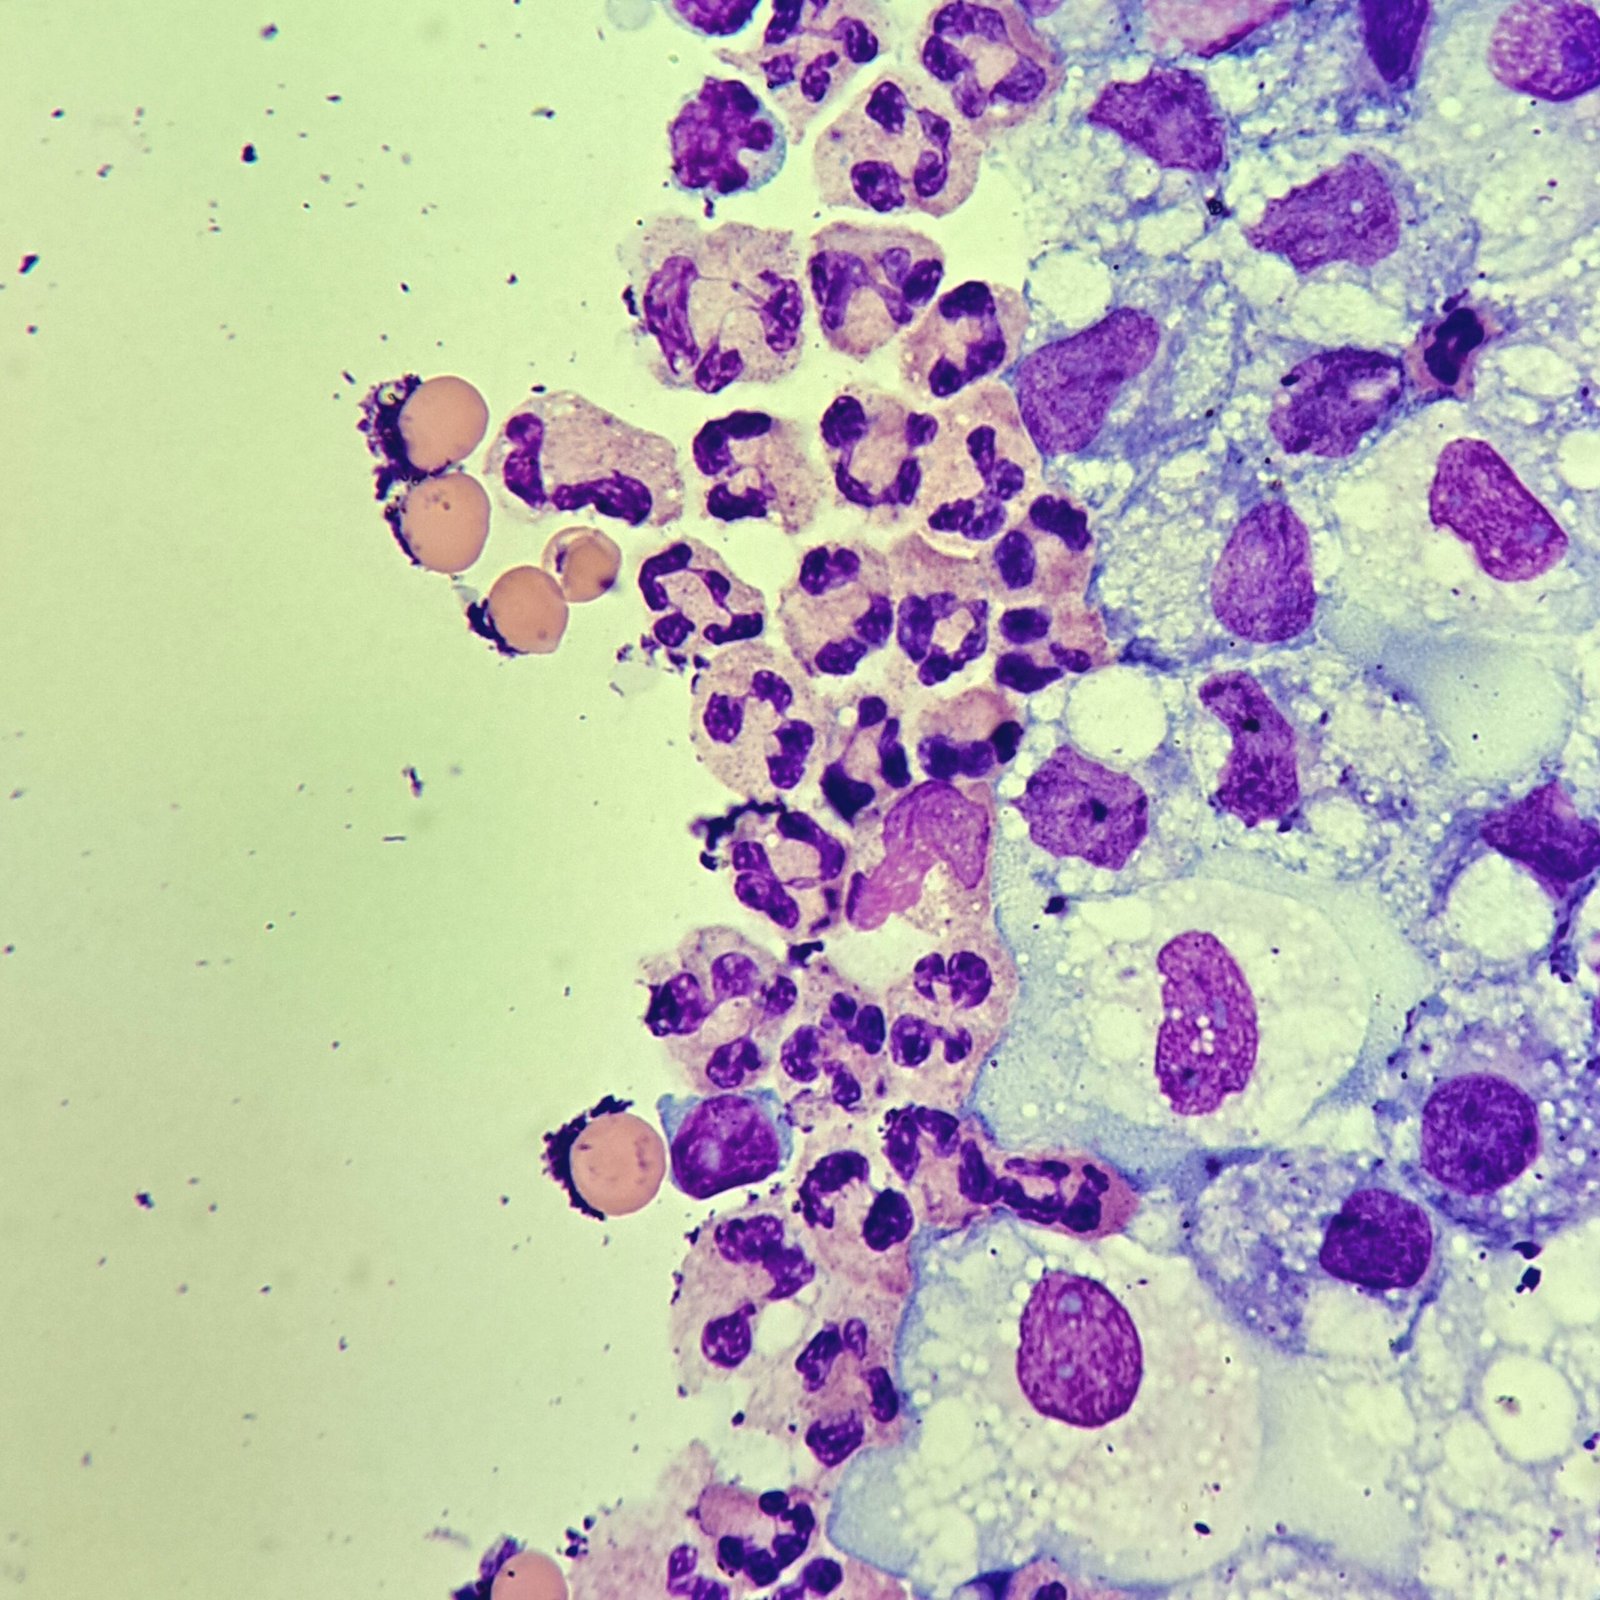

Macrophages are about the same size as mesothelial cells, so the two can often be confused. Macrophages can usually be differentiated by the presence of vacuoles and a lacey chromatin. If both cell types are present and differentiation is difficult, take a look around the slide to get an idea of each kind of morphology before starting a differential.

Both malignant cells and mesothelial cells can clump together. However, malignant cells will not have the windows between cells.